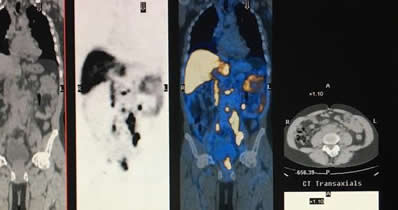

28 mil pacientes con cáncer fallecieron en el 2019 [...]